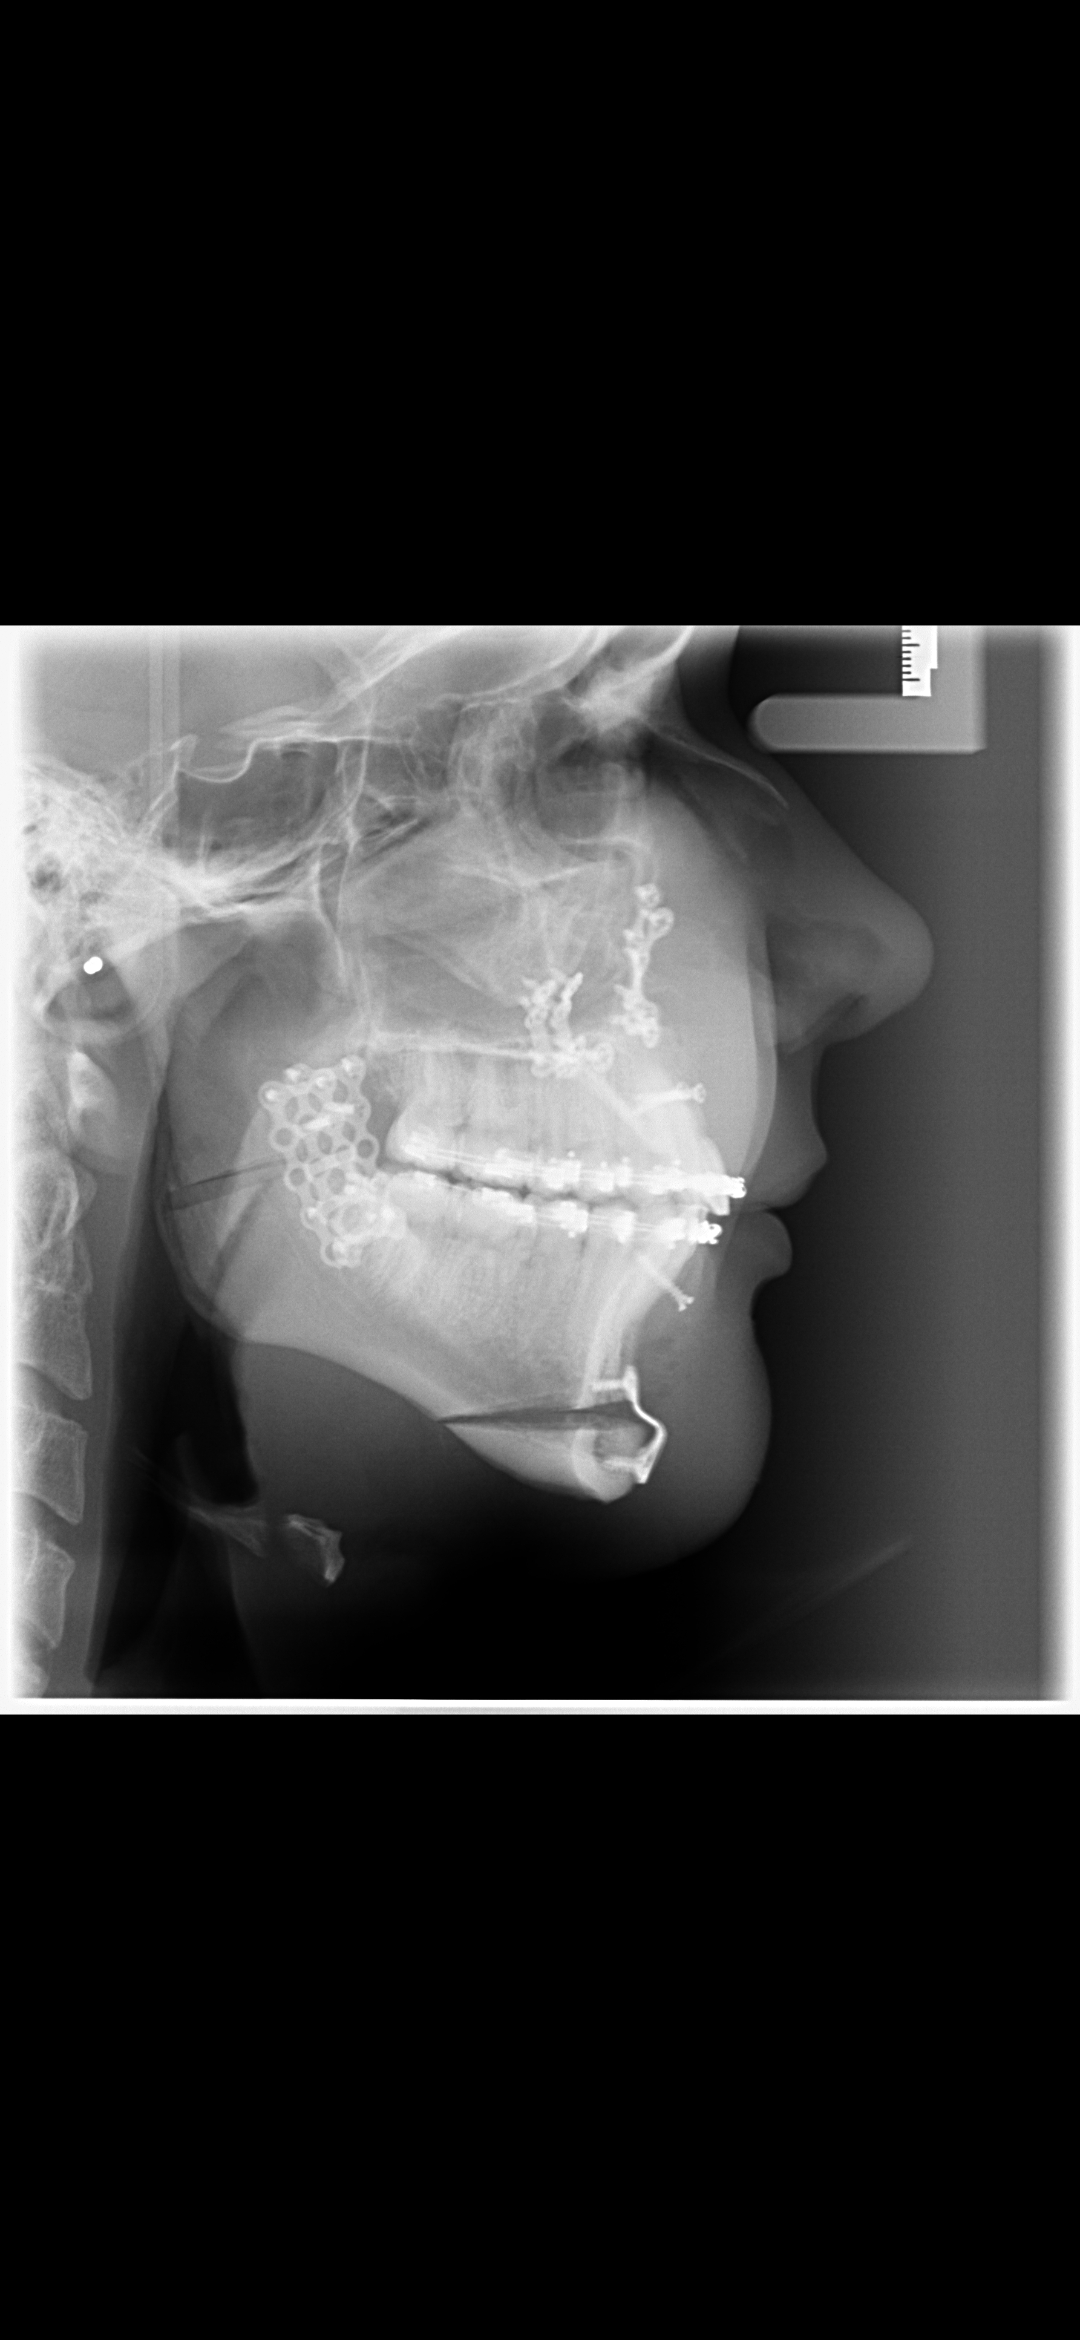

These are my CTs, how big do yall think i will ascend?

Before and after:

• Screenshot_20260207_101246_Gallery.jpg

Screenshot_20260207_101246_Gallery.jpg

548.8 KB · Views: 0